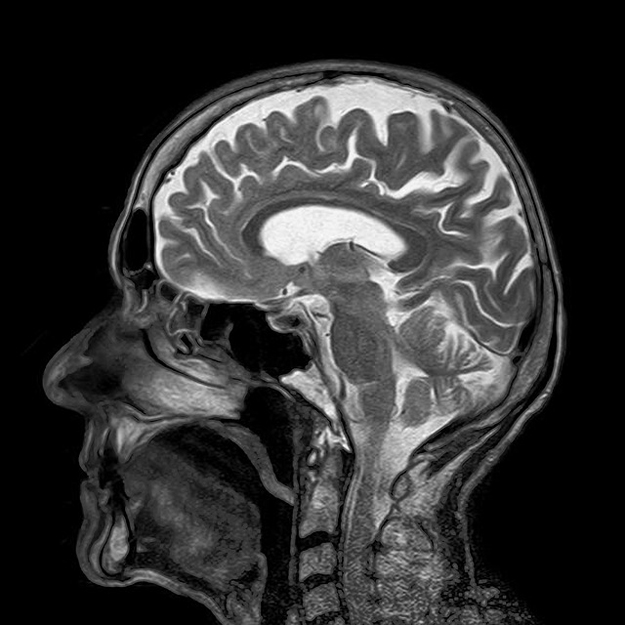

Illustration bannière : Médecins examinant une radio du crâne – © David Tadevosian Shutterstock